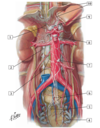

1

1 - superior mesenteric artery

2

2 - middle colic artery

3

3 - straight arteries (arteriae rectae)

4

4 - marginal artery

5

5 - right colic artery

6

6 - ileocolic artery (colic branch, ileal branch)

7

7 - appendicular artery

8

8 - superior rectal artery

9

9 - sigmoid arteries

10

10 - left colic artery

11

11 - inferior mesenteric artery

12

12 - jejnal and ileal (intestinal) arteries

2

2 - celiac trunk with common hepatic, left gastric, splenic arteries

4

4 - right renal artery

6

6 - common iiac arteries

7

37 - internal iliac artery

8

8 - external iliac artery